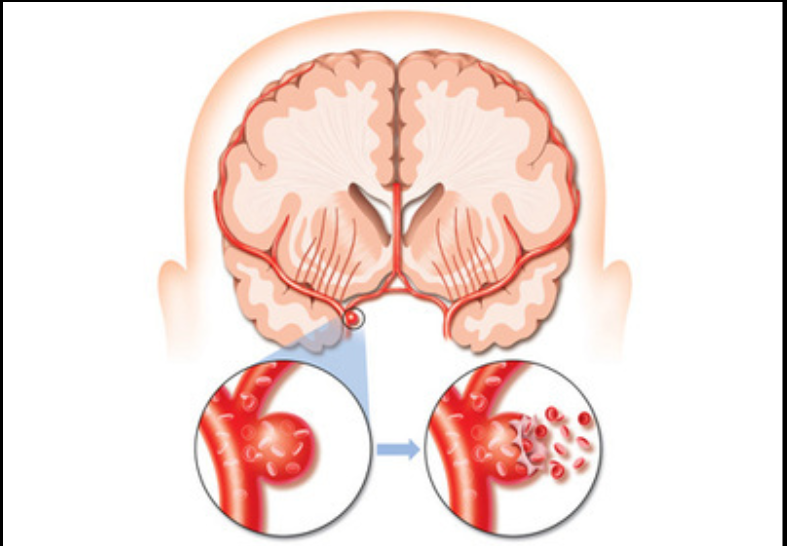

腦血管痙攣圖片

蛛網膜下腔出血引發腦血管痙攣

A:會發現蛛網膜下腔出血以後,大腦底部的,大血管發生狹窄,稱為腦血管痙攣,這是蛛網膜下腔出血最嚴重的併發症之一,發生率高達30%到90%。在腦血管痙攣,導致動脈口徑減少50%以上,即可發生。遠端腦組織灌注下降,甚至發生腦梗死,也就會出現腦血管痙……